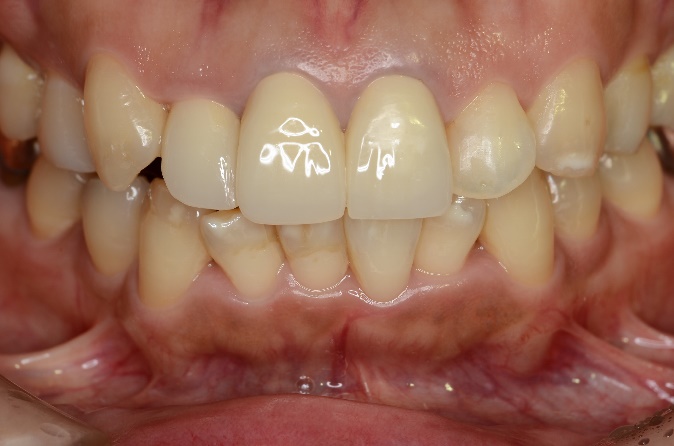

綺麗に被せているようにみえますが

39歳 女性 「前歯を綺麗にしたい」で来院されました。

セラミッククラウンとコンポジットレジンによる審美修復治療をおこないました。

治療前